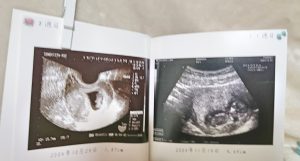

産婦人科でもらえるママのおなかの中にいた頃の写真だよ

今は、もうエコー写真も進化しているのかな?

友達から3Dのエコー写真を見せてもらったことがあります。

昔のエコー写真は、感熱紙で消えてしまうという話を聞いたので、急いでフォトブックにしました。

エコー写真をスキャナーで読み取って、データかしないといけません。

○週目の言葉の横に画像を入れたのもポイントです。